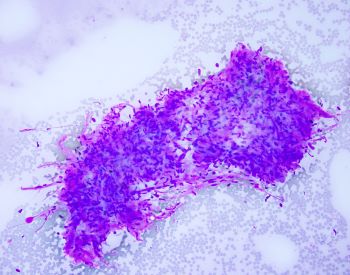

A fine needle aspiration of pancreatic head lesion/mass was performed and the specimen consists of loosely arranged small groups of spindle cells with scant cytoplasm and oval elongated and regular nuclei. Nucleoli are not seen. Ganglion cells are also present (two present in the lower half of the IHC image of the question).